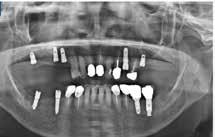

20–22. ábra: 2017-es, 2019-es és 2022-es panorámaröntgen-felvételek.

ságát egy ISO #15-ös endodonciai fájllal mértük 2 mm-re a marginális ínyszéltől meziálisan, disztálisan, illetve az implantátum tengelyében (mint referenciapont). A keratinizált íny szélességét parodontológiai szondával regisztráltuk a kiindulás és a kontrollvizsgálatok alatt. A méréseket elvégeztük a műtét előtt, közvetlenül utána, 4 héttel később, majd egy és két év elteltével. A klinikai paramétereket (keratinizált íny szélessége, lágyszövet volumen és recessziófedés) regisztráltunk a kiinduláskor és az utánkövetés időpontjai alatt. Kiinduláskor a feszes íny szélessége minimális volt (1 mm). A keratinizált ínyszélesség terén négy hétnél 2 mm-t sikerült nyerni, egy évnél 3 mm-t és öt év alatt 5 mm-t. A recessziót 100%-osan sikerült fedni 4 hét után, és ez nem változott sem egy év, sem öt év után.